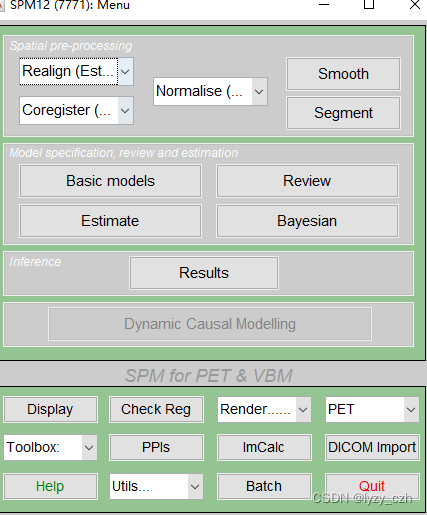

1) 打开matlab命令行输入spm pet,打开SMP12,界面如下